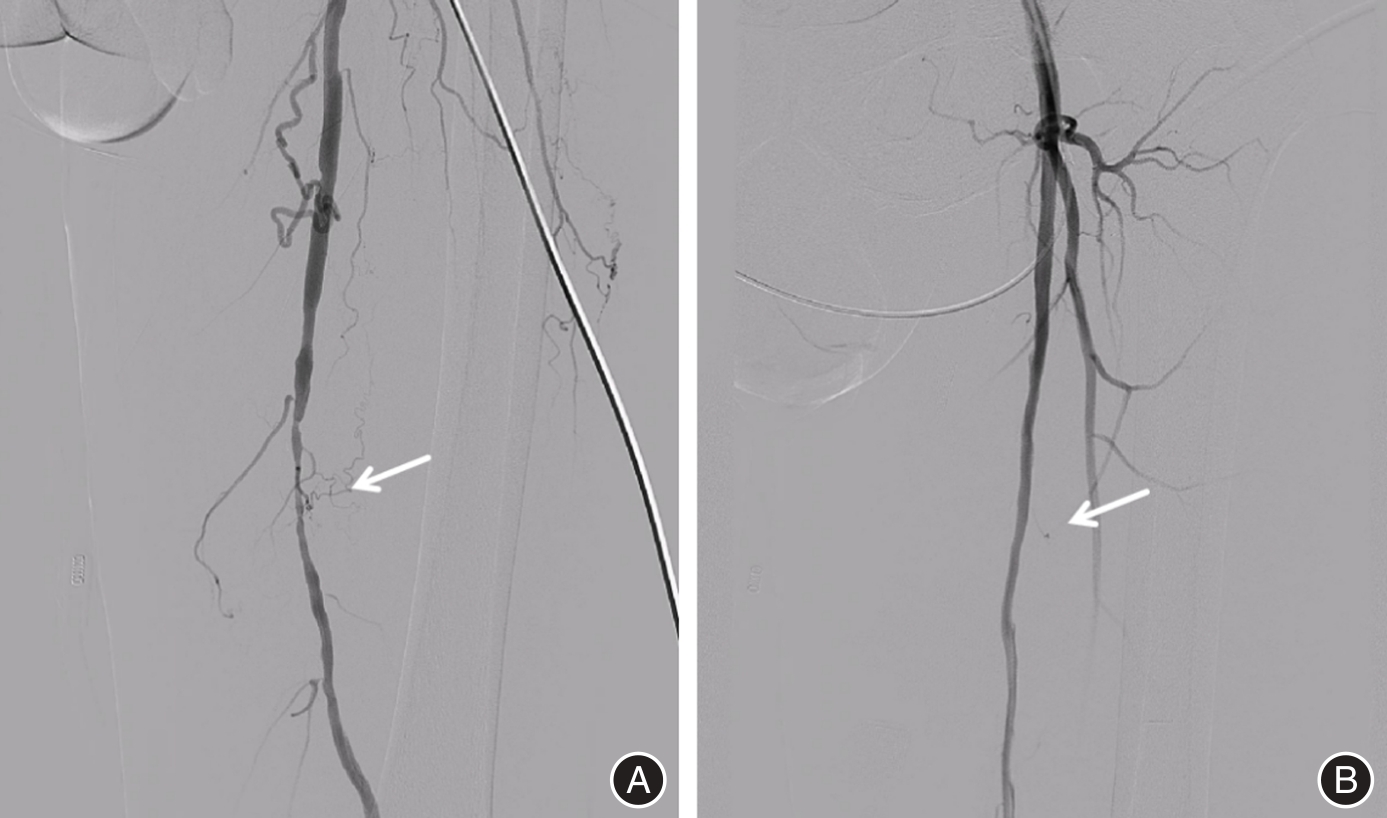

目的 探讨置管溶栓结合多种腔内介入术在改善下肢动脉硬化闭塞症患者动脉硬化指标中的应用。 方法 采用随机数字表法将2021年12月至2024年12月医院收治的下肢动脉硬化闭塞症患者125例分为对照组(63例,失访3例,最终60例)、观察组(62例,失访2例,最终60例)。对照组予以腔内介入治疗,观察组予以置管溶栓后行腔内介入治疗,两组均随访至介入治疗后6个月。比较两组临床疗效(治疗后6个月),行走受损问卷(WIQ)评分、Berg平衡量表(BBS)、视觉模拟评分(VAS)、Rutherford分级、血流动力学指标、动脉硬化指标、下肢神经传导速度、血清学指标(治疗前、治疗后6个月),并发症发生情况(随访期间)。 结果 治疗后6个月,观察组临床总有效率(93.33%)高于对照组(78.33%)(P < 0.05)。治疗后6个月较治疗前,两组行走距离、步行速度、爬梯能力评分均升高,观察组更高(P < 0.05)。治疗后6个月较治疗前,两组BBS评分均升高,观察组更高,VAS评分、Rutherford分级 > 3级的患者占比则均降低,观察组更低(P < 0.05)。治疗后6个月较治疗前,两组动脉血管内径均增厚,观察组更厚,血流量则均增加,观察组更多,血流峰速则加快,观察组更快,踝肱指数(ABI)则升高,观察组更高(P < 0.05)。治疗后6个月较治疗前,两组颈动脉内中膜厚度(IMT)均减小,观察组更小,脉搏波传导速度(PWV)则均减慢,观察组更慢,运动、感觉神经传导速度则加快,观察组更快(P < 0.05)。治疗后6个月较治疗前,两组血清血管内皮生长因子(VEGF)水平均升高,观察组更高,血清内皮素-1(ET-1)、超敏C反应蛋白(hs-CRP)、肿瘤坏死因子α(TNF-α)水平则均降低,观察组更低(P < 0.05)。随访期间,观察组并发症总发生率(3.33%)低于对照组(15.00%)(P < 0.05)。 结论 置管溶栓后行腔内介入治疗可稳定下肢动脉硬化闭塞症患者血流动力学指标,调整其动脉硬化指标,加快下肢神经传导速度,改善患者血管内皮功能,降低机体炎性因子水平,提高患者行走能力、运动功能,减轻患者疼痛感及下肢动脉缺血程度,疗效显著且能降低并发症发生率。

Objective To investigate the application of catheter-directed thrombolysis combined with various endovascular interventions in improving arteriosclerotic indices in patients with lower limb arteriosclerosis obliterans. Methods A total of 125 patients with lower limb arteriosclerosis obliterans admitted to the hospital between December 2021 and December 2024 were randomly assigned, using a random number table method, into a control group (n = 63, with 3 lost to follow-up, resulting in 60 evaluable cases) and an observation group (n = 62, with 2 lost to follow-up, resulting in 60 evaluable cases). The control group received endovascular interventional therapy alone, whereas the observation group underwent catheter-directed thrombolysis prior to the same endovascular intervention. Both groups were followed up for 6 months post-intervention. Outcomes assessed included clinical efficacy at 6 months after treatment, Walking Impairment Questionnaire (WIQ) scores, Berg Balance Scale (BBS) scores, Visual Analogue Scale (VAS) scores, Rutherford classification, hemodynamic indices, arteriosclerosis index, nerve conduction velocity in the lower limbs, serological markers (measured before treatment and 6 months post-treatment), and incidence of complications during follow-up. These outcomes were compared between the two groups. Results Six months after treatment, the total clinical effective rate in the observation group (93.33%) was significantly higher than that in the control group (78.33%) (P < 0.05). Compared with pre-treatment levels, both groups showed improvements in walking distance, walking speed, and stair-climbing ability, with greater gains observed in the observation group (P < 0.05). The Berg Balance Scale (BBS) scores increased in both groups, with a more pronounced improvement in the observation group (P < 0.05). Additionally, the proportion of patients with Visual Analog Scale (VAS) scores and Rutherford classification exceeding grade 3 decreased, with a lower proportion in the observation group (P < 0.05). The arterial lumen diameter increased in both groups, while blood flow volume and peak velocity improved more significantly in the observation group, along with a greater increase in ankle-brachial index (ABI) (P < 0.05). Carotid intima-media thickness (IMT) decreased in both groups, with a greater reduction in the observation group; pulse wave velocity (PWV) slowed, and both motor and sensory nerve conduction velocities increased, with more favorable changes in the observation group (P < 0.05). Serum levels of vascular endothelial growth factor (VEGF) increased in both groups, particularly in the observation group, while levels of endothelin-1 (ET-1), high-sensitivity C-reactive protein (hs-CRP), and tumor necrosis factor-α (TNF-α) decreased, with more marked reductions in the observation group (P < 0.05). During the follow-up period, the overall complication rate in the observation group (3.33%) was significantly lower than that in the control group (15.00%) (P < 0.05). Conclusions Endovascular interventional therapy following catheter-directed thrombolysis can stabilize hemodynamic parameters in patients with lower limb arteriosclerosis obliterans, modulate atherosclerotic markers, accelerate lower limb nerve conduction velocity, improve vascular endothelial function, reduce systemic inflammatory factor levels, enhance walking capacity and motor function, alleviate patient pain, and mitigate the degree of lower limb arterial ischemia. This combined approach demonstrates significant therapeutic efficacy and reduces the incidence of complications.